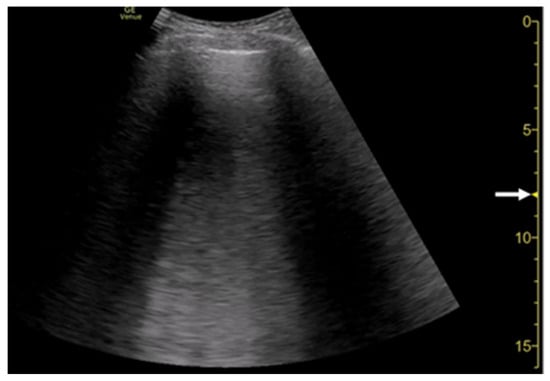

3.4. Selection of Transducers